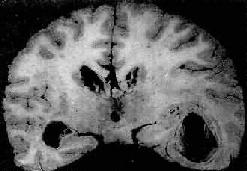

肉眼观,脑脊膜血管高度扩张充血,病变严重的区域,蛛网膜下腔充满灰黄色脓性渗出物,覆盖着脑沟脑回,以致结构模糊不清(图16-10),边缘病变较轻的区域,可见脓性渗出物沿血管分布。在渗出物较少的区域,软脑膜往往略带混浊。脓性渗出物可累及大脑凸面矢状窦附近或脑底部视神经交叉及邻近各池。由于炎性渗出物的阻塞,使脑脊液循环发生障碍,可引起不同程度的脑室扩张。

化脓性脑膜炎

图16-10 化脓性脑膜炎

蛛网膜下腔内有多量脓液堆积以致大部分脑表面的沟回结构不清;脑膜血管高度扩张充血